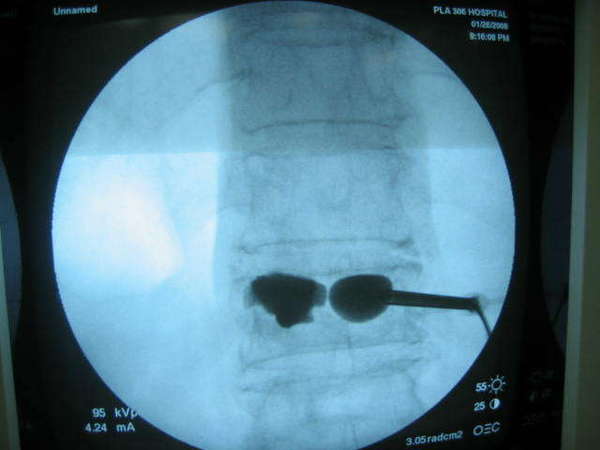

治疗----后路经皮穿刺、球囊扩张、椎体成型术

比较手术前后显示T12骨折椎体高度恢复,脊柱后凸畸形获得明显改善,填充骨水泥到位并均匀,无渗漏现象.